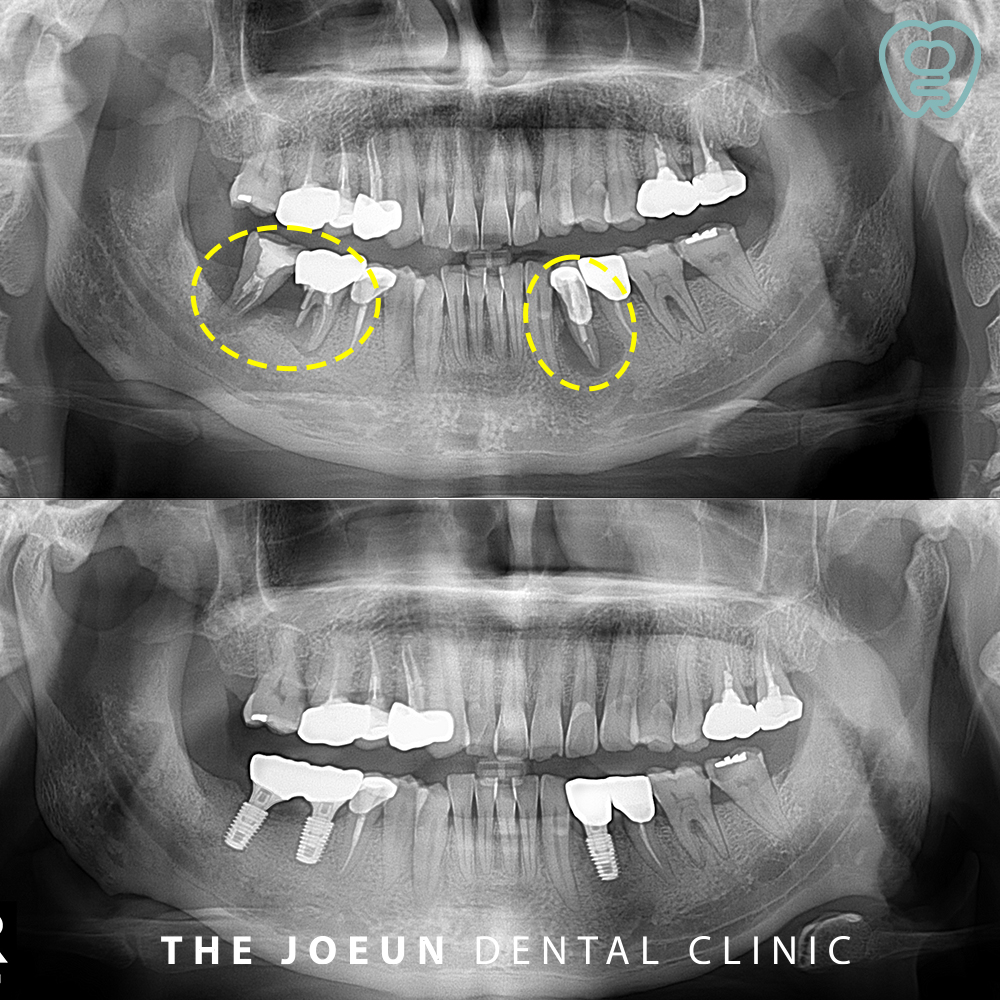

오늘은 심한 골 파괴로 인해 발치 후 뼈 이식을 선행한 뒤, 임플란트를 식립하여 완성하신 환자분을 소개해 드리도록 하겠습니다. 환자분께서는 아래쪽 치아 잇몸이 피곤하거나 컨디션이 좋지 않을 때 붓기도 하고 양치할 때 피도 나오신다며 내원해 주셨습니다.

파노라마 사진을 촬영해 보았을 때 확연하게 양쪽 아래 큰 어금니와 작은 어금니 부위 크라운으로 수복되어 있는 치아들의 뿌리에 커다란 염증으로 인해 이미 잇몸뼈를 많이 녹인 상태임을 확인할 수 있었습니다. 이미 많은 시간이 지나 남아 있는 치조골 유지를 위해 발치 후 치조골 이식을 진행하여 임플란트 식립을 위한 상태를 만들어준 후 임플란트를 진행하는 것으로 계획을 수립하였습니다.

원인이 되는 치아들을 발치한 후 뼈이식을 먼저 진행하였습니다.

뼈이식을 하고 약 6개월 뒤, 검진 후 임플란트 식립을 진행하였습니다.

잇몸뼈가 심하게 파괴되어 걱정했지만 안정적으로 최종 보철물까지 완료하였습니다.